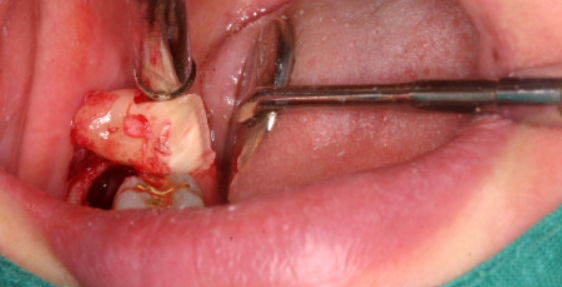

매복된 치아를 제거하는 것은 까다롭고 위험한 수술 절차입니다. 따라서 수술 후 관리가 매우 중요합니다. 지침을 잘 따르면 불필요한 통증과 감염 및 부종의 합병증을 최소화할 수 있습니다. 어떻게 관리하느냐가 회복의 지름길이지요!

1. 발치 수술 직후 주의사항

수술 부위에 거즈 패드를 대고 30분 동안 단단하게 물린 상태로 유지해야 합니다. 잇몸에서 다량의 출혈이 생기기 때문에 반드시 주의해야 하는 부분입니다. 그리고 수술 후 상처 부위를 심하게 헹구거나 만지는 것은 피해야 합니다. 이것은 형성된 혈전을 제거하여 출혈이 멈추지 않을 수 가 있거든요. 발치 후 통증은 아주 극심합니다. 고통을 견디기 어려우신 분은 1시간 이내에 처방된 진통제를 복용하세요. 마치가 풀리기 시작하면 통증이 생기기 때문에 1시간 이전에 진통제를 복용해야 효과가 있습니다.